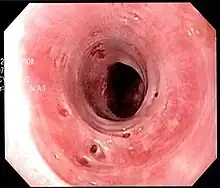

Endoscopic image of esophageal intramural pseudodiverticulosis demonstrating the flask-like outpouchings of the esophageal wall.

Esophageal intramucosal pseudodiverticulosis is typically diagnosed at the time of endoscopy of the esophagus. Endoscopy shows evidence of the pseudodiverticulae, which are typically numerous, appear like pits in the wall, and may be preferentially located in the upper esophagus.[3][5] The mucosal lining of the esophagus may be inflamed, and this can be seen on endoscopy or on biopsy; the mucosa, however, may also be normal if esophagitis is not the cause of the pseudodiverticulosis. The condition must also be excluded from esophageal cancer, which may be done at the time of endoscopy, or which may require esophageal biopsy.[3]